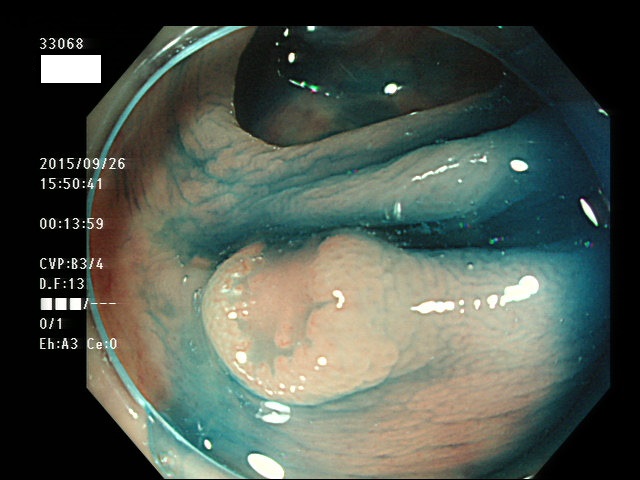

上記100名より抽出した平坦・陥凹型腺腫(=癌化の危険が高いが見落としやすい病変)の内視鏡写真

33003 33004 33005 33006 33007 33008 33009 33010 33011 33012 33013 33014 33015 13306 33018 33021 33024 33025 33026 33029 33030 33031 33032 33033 33036 33038 33039 33041 33042 33045 33046 33048 33051 33053 33054 33055 33057 33060 33063 33066 33068 33069 33071 33072 33074 33077 33078 33080 33086 33088 33089 33090 33091 33093 33095 33096 ・・・・・・の56名